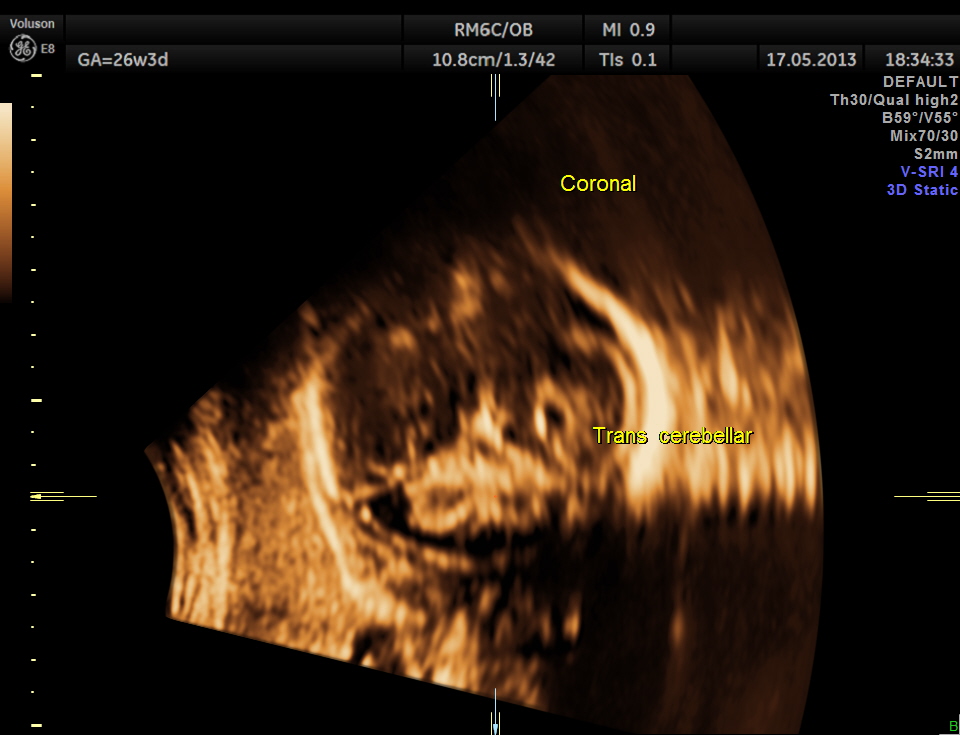

Cerebellum appears relatively smaller and corresponds to a GA of 22 to 23 weeks. Usually the cerebellum corresponds very closely to the GA and would be very useful to follow in cases of IUGR.

Cerebellum was < 2.3 %tile , suggestive of possible cerebellar hypoplasia. Unfortunately this patient was lost for follow up .